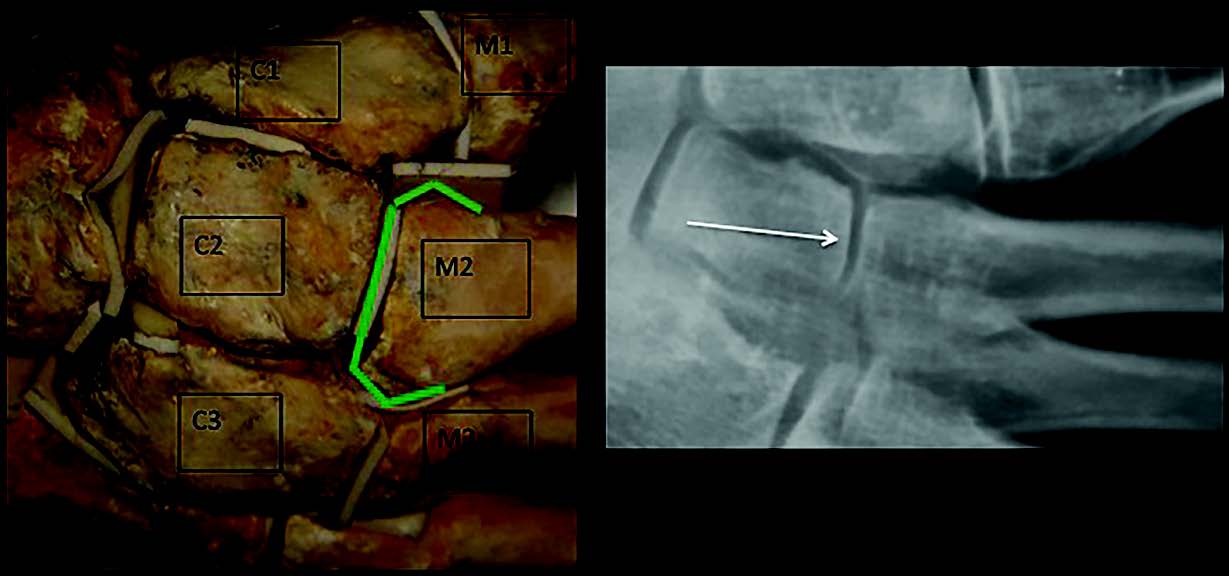

Mise au point Le syndrome du deuxième rayon , Cyrille Cazeau Hôpital Hôtel-Dieu, 1 place du Parvis de Notre-Dame, 75004 Paris, France , Tony Chevalier Université de Perpignan, Via Domitia UMR 7194, CERP Tautavel, France 🖂 tony.chevalier@cerptautavel.com N°238 - Novembre 2014 - Cahier N°2 ● 21 min de lecture